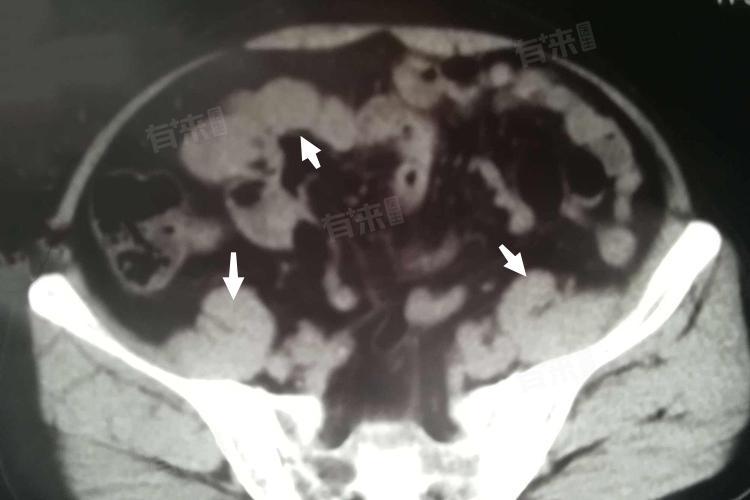

2、肿块:在脂肪疝发生部位,可触及大小不等的肿块。肿块质地一般较软,边界相对清晰,多呈圆形或椭圆形。肿块在站立或增加腹压时更为明显,可突出于皮肤表面,而在平卧或用手按压时,部分肿块可回纳入腹腔或筋膜下。例如,在腹部出现的脂肪疝,患者或医生在检查时,能清晰摸到皮下的肿块,当患者变换体位时,肿块的大小和位置会发生相应变化。随着病情进展,脂肪疝的肿块可能会逐渐增大。这是因为疝出的脂肪组织不断增多,且周围组织可能会因长期受刺激而发生炎症反应、纤维化等改变,导致肿块边界逐渐变得不那么清晰,与周围组织粘连,活动度减小。部分患者可能会因肿块增大,影响外观,产生心理负担。